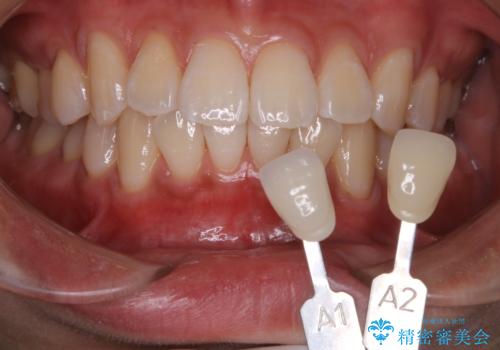

一見きれいに見える歯でも、染め出し(歯垢染色液)を使うとこのように歯と歯茎の境目や、歯と歯の間などに磨き残しがあることがわかります。歯磨きには、いつも気をつけているから磨き残しはナシと思っていても、実際完璧に磨ききることはなかなか難しいです。歯科医院にて、専門の機械で定期的なPMTCを行うことが大切です。